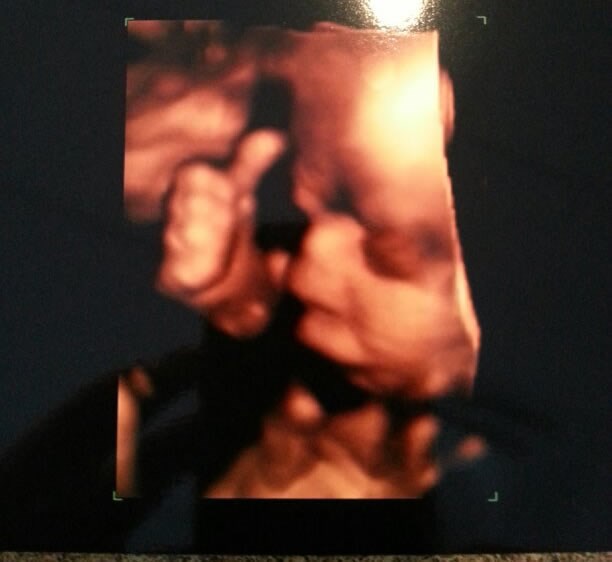

Nerođena beba dala "palac gore" preko 3D ultrazvuka